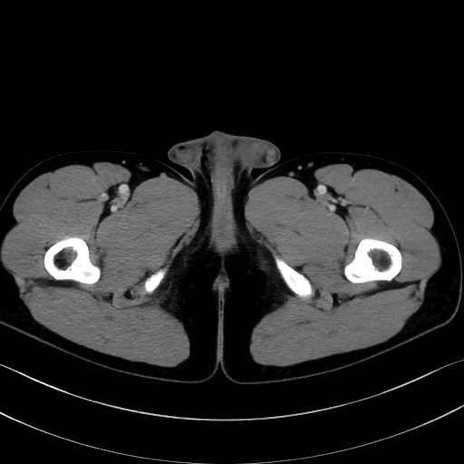

内閉鎖筋(obturator internus) のCT画像の解剖

内閉鎖筋 (Obturator internus)

外閉鎖筋 (Obturator externus)

大腿方形筋 (Quadratus femoris)